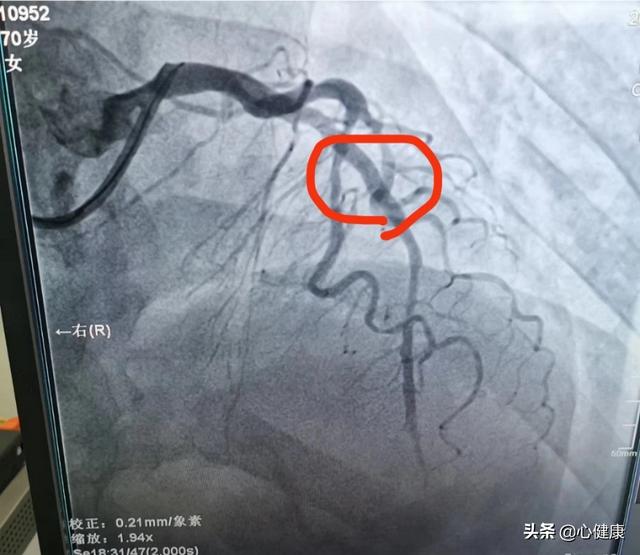

L'obstruction des branches descendantes antérieures est généralement le résultat d'un infarctus aigu du myocarde, au cours duquel le patient ressent une oppression thoracique, une douleur thoracique et des sueurs froides. La douleur thoracique dure généralement longtemps et n'est pas soulagée. Les enzymes myocardiques sont élevées et la coronarographie révèle une sténose de 100 % des branches descendantes antérieures. Dans ce cas, les vaisseaux sanguins sont occlus et le flux sanguin est interrompu, ce qui entraîne une incapacité à fournir du sang correctement. Cela entraîne une nécrose du myocarde. Certains patients ne se sentent pas aussi mal en raison de leur propre système circulatoire collatéral plus performant.

Comment le sang est-il irrigué après une occlusion de la branche descendante antérieure ?

Lorsque l'infarctus aigu du myocarde survient après une occlusion de la branche descendante antérieure, la thrombolyse est nécessaire dès que possible, à la première occasion, pour ouvrir le vaisseau et sauver le myocarde ischémique, car plus le temps passe, plus la zone de nécrose myocardique s'étend. Cela signifie également que le temps, c'est le myocarde, et que le myocarde, c'est la vie. Si le vaisseau est chroniquement occlus, il est important de réfléchir à la manière de maintenir la stabilité de l'état et de retarder l'apparition de la maladie. Dans ce cas, il convient de prendre davantage de médicaments cardiotoniques, diurétiques et vasodilatateurs.